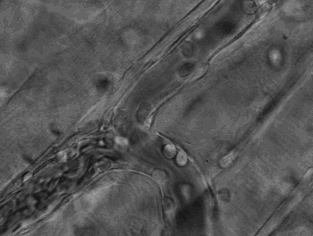

3.這張動(dòng)圖顯示的是嗜酸性粒細(xì)胞在趨化作用的“感知”下逐漸聚集到一只秀麗隱桿線蟲(chóng)周圍并對(duì)它進(jìn)行攻擊的過(guò)程。有“成千上萬(wàn)”的嗜酸粒細(xì)胞圍聚在線蟲(chóng)周圍,就像一群螞蟻,善打“包圍戰(zhàn)”。